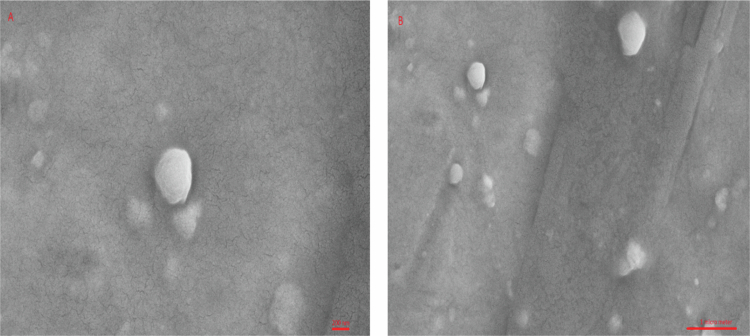

Materials and methods: The size and particle dispersion index (PDI) of caffeic acid-containing niosome vesicles were measured after their production. The zeta potential was measured using a Zetasizer Nano ZS, and the amount of nano-caffeic acid released from the vesicles was measured. Candida isolates were cultured in Malt Extract Agar medium. Nystatin, fluconazole, caffeic acid and nano-caffeic acid were studied according to the Clinical and Laboratory Standards Institute (CLSI) protocol (M27-A3/S4), a broth microdilution test was performed, and the minimum inhibitory concentration (MIC) was determined. The data were analyzed using the Mann‒Whitney and Kruskal‒Wallis tests.

Results: The optimal formulation had 100 mg Tween 60, 100 mg Span 60, 200 mg cholesterol, a size of 271.83 ± 3.11 nm, a PDI of 0.21 ± 0.02, a zeta potential of 5.58 ± 0.47 mV and an encapsulation efficiency (EE%) of 42.34 ± 4.34%. The size, absolute zeta potential and EE% increased significantly with increasing cholesterol content from zero to 200  mg (P < 0.05). Caffeic acid, nano-caffeic acid, carrier, fluconazole and nystatin had the lowest to highest antifungal activity, respectively.